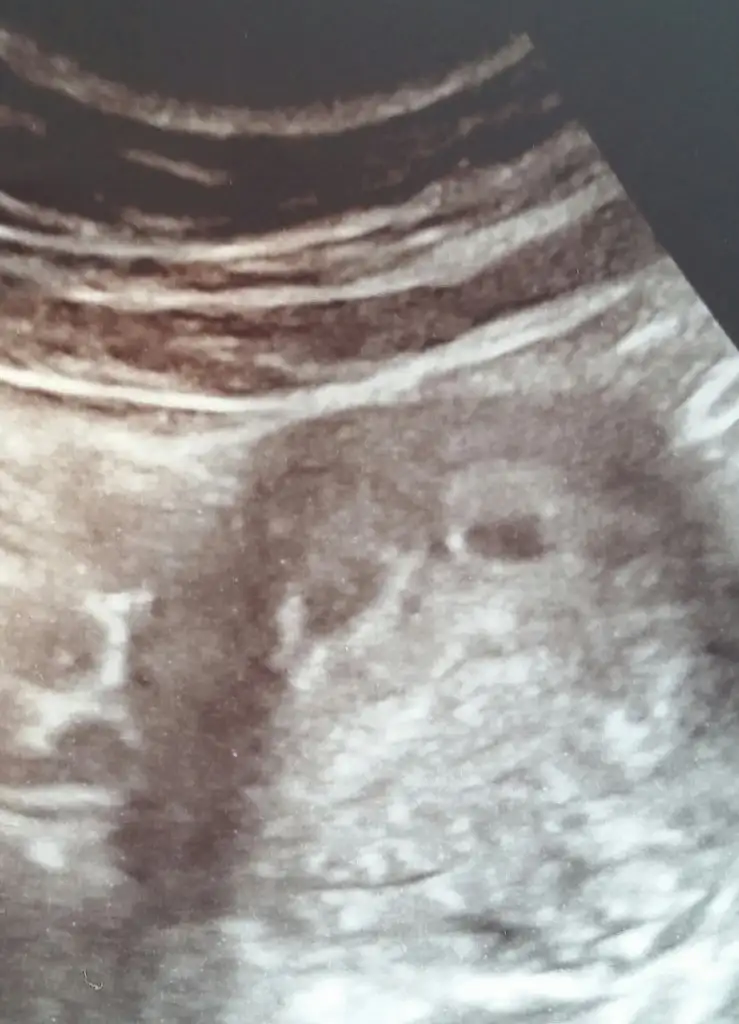

Canım benim Allah nasip ederse ikizlerim olacak. Alttaki ultrason görüntüsünde sağdakiler benim miniklerim. 5+1 günlük. seninkisi tek gibi ama ilk kontrolde tek kese görüp ikinci keseyi sonra gören bir çok kişi de olabiliyor. Allah gönlüne göre versin inşallah sağlıklı olsunlar da bir iki farketmez değil mi ama☺